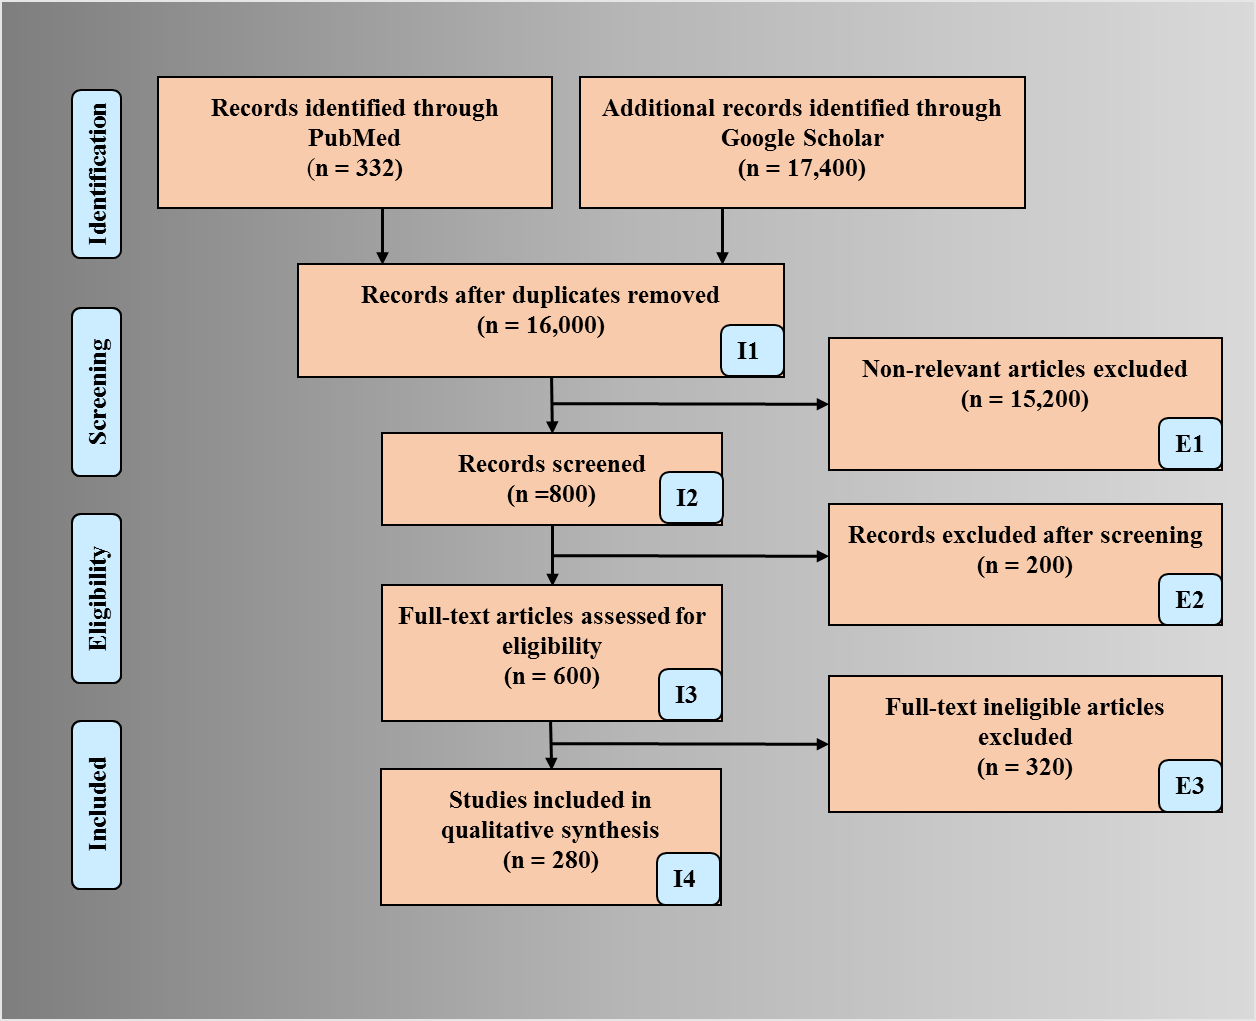

PRISMA model was adapted for the search strategy (Fig. 2). We used several repositories to retrieve the maximum amount of relevant information as required. PubMed and Google Scholar were used for searching the keywords such as “nutrition and atherosclerosis”, “nutrition, atherosclerosis, myocardial infarction”, “nutrition stroke atherosclerosis”, “atherosclerosis risk factors”, “nutrition, ethnicity, geographical effects and heart disease”, “nutrition obesity diabetes atherosclerosis”, “arterial imaging in atherosclerosis”, “atherosclerotic tissue classification and characterization”, “plaque tissue characterization”, “diet and atherosclerosis”, “cardiac injury and COVID-19”, “atherosclerosis and COVID-19”. We found about 332 articles on PubMed and about 17,400 articles on Google scholar. A total of 16,000 studies were identified, and duplicates were removed using the feature called “Find Duplicates” in EndNote software by Clarivate Analytics [47]. After applying advanced filters such as time and relevance, this narrowed down to 600 articles. The three exclusion criterias were (i) studies not related, (ii) non-relevant articles, and (iii) having insufficient data. This excluded 15,200,200, and 320 studies (marked as E1, E2, and E3), leading to the final selection of 280 studies.

Fig. 2.

Fig. 2.PRISMA model depicting search strategy.